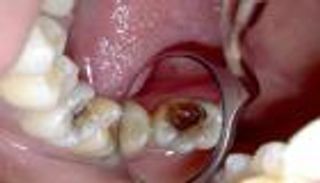

ويتم إجراء علاجات قناة الجذر بشكل روتيني لدى ملايين المرضى، ويتضمن الإجراء إزالة الأنسجة الرخوة المصابة داخل السن، والتي تسمى اللب، وغسل السن بالمضادات الحيوية أو المواد الكيميائية لقتل البكتيريا المسببة للعدوى، لكن في كثير من الأحيان يفشل العلاج في إزالة جميع البكتيريا تمامًا- خاصة البكتيريا المقاومة للمضادات الحيوية مثل المكورات المعوية البرازية، والتي تظل مخفية داخل القنوات المجهرية في السن، والتي تسمى الأنابيب العاجية.

ويقول شانموخ سرينيفاس، الباحث المشارك في مركز علوم وهندسة النانو بالمعهد الهندي للعلوم: "الأنابيب العاجية صغيرة جدًا وتوجد البكتيريا في عمق الأنسجة، والتقنيات الحالية ليست فعالة بما يكفي للذهاب إلى الداخل وقتل البكتيريا".